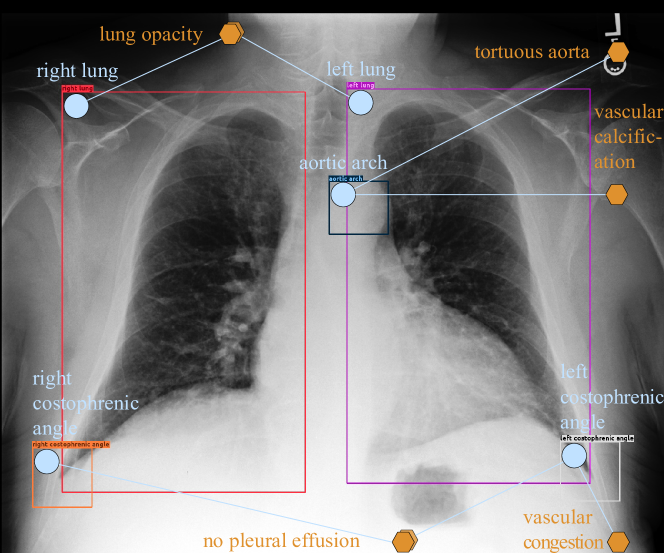

Refer to caption

Figure 4: An example of reports generated by different models. Most medical terms are highlighted. Abnormal terms are in bold.

4.5 Qualitative Results

We present qualitative results to further demonstrate the effectiveness of SGRRG𝑆𝐺𝑅𝑅𝐺SGRRG. As illustrated in Figure 4, SGRRG𝑆𝐺𝑅𝑅𝐺SGRRG appears to better capture disease information and generate abnormal descriptions, e.g., “there is mild pulmonary vascular congestion, the cardiac silhouette is top normal to mildly enlarged and the aorta is calcified and tortuous.”, compared to the Base𝐵𝑎𝑠𝑒Base model. To investigate whether this improvement is truly related to the radiology scene graph, we also visualize the predicted scene graphs with anatomical finding attributes in which the abnormal observations, e.g., “lung opacity", “atelectasis", “vascular congestion" and “tortuous aorta", are present. Clearly, such abnormal medical observations are vital in report generation. Moreover, the average number of words in reports generated by SGRRG𝑆𝐺𝑅𝑅𝐺SGRRG is 14.514.514.5% longer than the base model, i.e., 50.550.550.5 vs 44.144.144.1 (53.653.653.6 in ground truth reports), indicating that SGRRG𝑆𝐺𝑅𝑅𝐺SGRRG could generate more descriptive reports. These results further verify the potential of the radiology scene graph and our proposed framework. Further examples are given in the supplementary files.